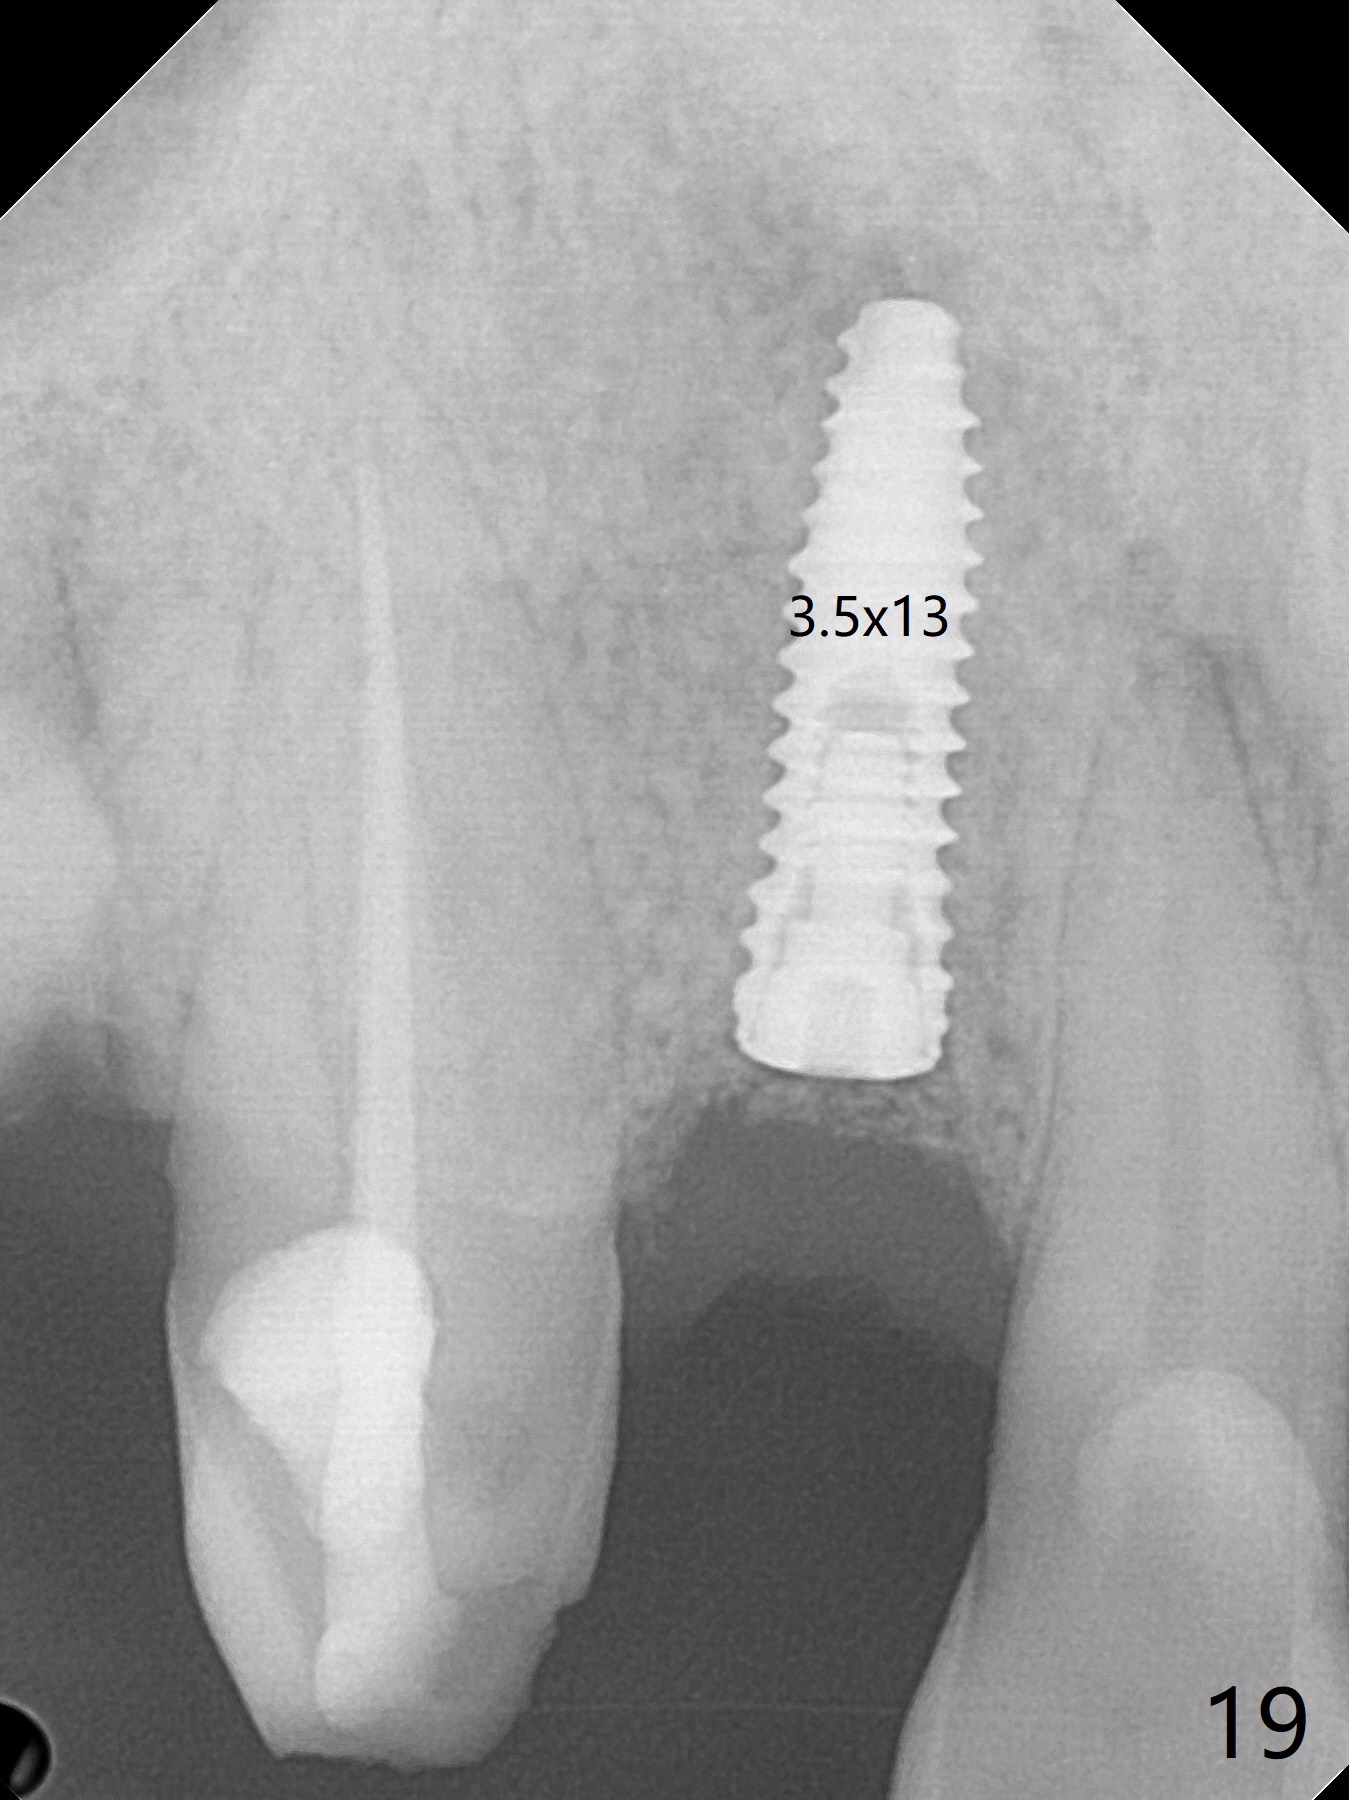

An apical abscess is present when the patient returns for immediate implant at #7 (Fig.1 *); a 2nd challenge is deep bite. After smooth extraction, the apical buccal plate is found to be perforated. Following debridement, a piece of gauze is placed in the apical defect for hemostasis, while osteotomy is initiated palatal (Fig.2). The apical defect seems to be extensive (Fig.3 yellow dashed line). A new trajectory is intended (red arrow) without much success. Before implant placement, bone graft is placed in the apical defect defect area, while a drill (Fig.4 D) is inserted in the finished osteotomy (Fig.5 O). In spite of seemingly large apical defect, the buccal crest bone exists (Fig.4 x). A 3x14(2) mm 1-piece implant is placed with stability; the first round of bone graft is apparently around the apical portion of the implant (Fig.6 *). The coronal end of the implant has to be adjusted several times buccopalatally to accommodate the deep bite. A 2nd round of bone graft following an immediate provisional closes the coronal space of the socket (Fig.7 *). CT will be taken to show the bone graft to repair the buccal plate defect when the patient returns for postop follow-up. In fact the defect is minimal in CT a month ago. The fistula does not disappear 1 week postop, but it is non tender (Fig.8). The patient complains of asymptomatic swelling in the right nostril. CT shows that the large buccal perforation is repaired with large amount of bone graft (Fig.9,10 *). It would be nicer to place the implant slightly more buccal apically (Fig.11 red lines; Fig.12 (preop design)). The buccoapical fistula disappears nearly 1 month postop (Fig.13). The apparently "lifeless" bone graft seems to be harmonious with the surrounding tissue (Fig.14). The periimplant gap reopens with implant mobility nearly 4 months postop (Fig.15), which is related to micro-movement associated with the immediate provisional. The latter is removed. A larger 2-piece implant will be placed in a 2-staged manner if needed (Fig.16). In fact the 3x14 mm straight 1-piece implant (Fig.17) has no mobility when it is retightened, but the trajectory remains buccal. Incision shows that there is no implant thread exposure. A 3x14 mm 15 degree angled 1-piece dummy implant is able to establish the correct trajectory, but there is no occlusal clearance (Fig.18). Micromovement during osteointegration may recreate loosening. Finally using Lindamann bur, the osteotomy is changed so that a 3.5x13 mm 2-piece implant does not need an angled abutment to establish occlusion (Fig.19). There is one palatal thread exposure. Allograft is placed circumferentially, followed by Human Amnion-Chorion Allograft and Collagen Plug. The wound does not heal 8 days postop (Fig.20), as related to the age (79 years old)? The wound appears to heal with a membrane on the surface (Amnion-Chorion one?) 3 weeks postop (Fig.21). The ridge looks wide 3.5 months postop (Fig.22,23). A 4.5x5.5(3) mm appears to be seated incompletely with a gap between the abutment and the implant (Fig.24<). A provisional is fabricated after heavy palatal reduction. Two months later, the provisional fractures. After repositioning the abutment with complete seating and torque (Fig.25), impression is taken. Although the buccal plate is concave, the gingiva remains healthy 10 months post cementation (Fig.26,27).